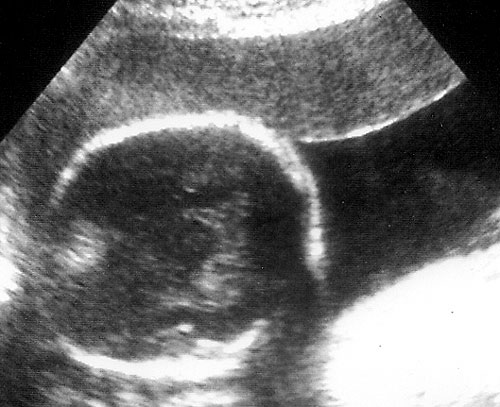

Normal BPD at level of thalami with cavum seen. - Falx: midline and perpendicular to angle of insonation. (Simpson GF, Filly RA. Comparison of fetal head circumference measurements using standard and long linear array transducers. J Diagn Med Sonogr 1988;4:2)